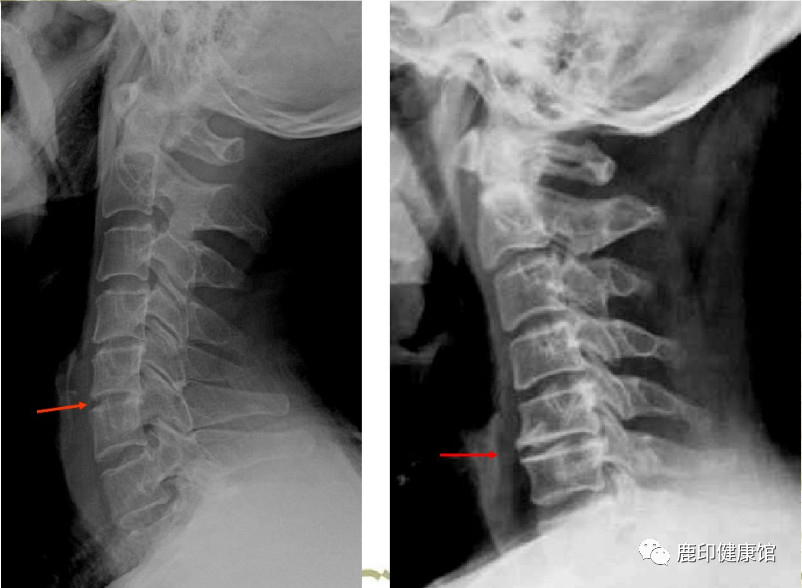

颈部疼痛,是现代人常见的问题。遇到这种不适,很多人按部就班去医院挂号、就诊、检查。结果片子一出现,就看到自己“颈椎生理弯曲变直,颈椎体边缘骨质增生变尖。”

随着年龄的增生,人体的关节会发生退变而稳定性下降,为了加强稳定,在某些骨头的边缘增加钙的沉积,形成骨突起,如果凸起的结构形态像刺,则称为骨刺。就像一栋危楼,在开裂的地方需要加固,以稳定整体结构。

另外,长时间维持持于某种姿势,如使用电脑、低头看手机、躺着看电视等,因受力不平衡引起肌肉的牵拉或撕脱、出血,血肿机化,则会形成刺状或唇样的骨质增生。